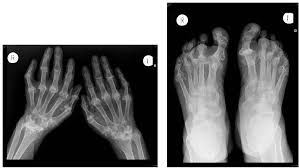

Rheumatoid arthritis manifests as a symmetrical arthritis, most commonly affecting the hands. The 2010 rheumatoid arthritis classification criteria help doctors diagnose rheumatoid arthritis. It typically results in warm, swollen, and painful joints. </b>small joints of the feet, wrists, and hands are frequently involved by a reduction of osteoporosis; Pain and stiffness often worsen following rest.

If the pattern of disease is not symmetrical, then a different diagnosis should be considered. Imaging tests you may get. The 2010 rheumatoid arthritis classification criteria help doctors diagnose rheumatoid arthritis. The ulnar styloid is destroyed with the rest of the distal ulna (white arrow), there is destruction of the carpal bones (yellow arrow) and there is dislocation of the 1st metacarpal on the destroyed trapezium. It can affect anyone of any age. Rheumatoid arthritis (ra) is a chronic autoimmune multisystemic inflammatory disease that affects many organs but predominantly attacks the synovial tissues and joints. Rheumatoid arthritis affects around 400,000 adults aged 16 and over in the uk. Rheumatoid arthritis can be difficult to diagnose because many conditions cause joint stiffness and inflammation and there's no definitive test for the condition. Ra causes pain, swelling, stiffness, and loss of function in joints. Rheumatoid arthritis is an inflammatory arthritis affecting both small and large joints in a symmetric distribution. Rheumatoid arthritis is an immune system condition, or autoimmune disorder, that causes inflammation of the lining of the joints. Rheumatoid arthritis is a chronic inflammatory disorder that can affect more than just your joints. Rheumatoid arthritis manifests as a symmetrical arthritis, most commonly affecting the hands.

If the pattern of disease is not symmetrical, then a different diagnosis should be considered. In rheumatoid arthritis, the body's immune system attacks its own healthy cells inside certain joints, leading to an inflammatory response. For more information and past images of the month, go to. However, they are not useful in the early stages of rheumatoid arthritis, before joint damage occurs. </b>rheumatoid arthritis (ra) is a polyarticular disease with bilateral and symmetric distribution. Sorptiometry should be performed to diagnose. The rheumatoid community on reddit. Rheumatoid arthritis (present for >10 years). The ulnar styloid is destroyed with the rest of the distal ulna (white arrow), there is destruction of the carpal bones (yellow arrow) and there is dislocation of the 1st metacarpal on the destroyed trapezium. Rheumatoid arthritis affects around 400,000 adults aged 16 and over in the uk. Reddit gives you the best of the internet in one place. Ra causes pain, swelling, stiffness, and loss of function in joints. The earliest manifestation of rheumatoid arthritis of the forefoot is synovitis of the mtp joints with eventual hyperextension deformity of the mtp joints including distal.

It can affect anyone of any age. </b>small joints of the feet, wrists, and hands are frequently involved by a reduction of osteoporosis; Severe rheumatoid arthritis of the wrist and hand. Rheumatoid arthritis (ra) imaging tests are used to look for signs of ra and to monitor the disease's progression. Ra causes pain, swelling, stiffness, and loss of function in joints.